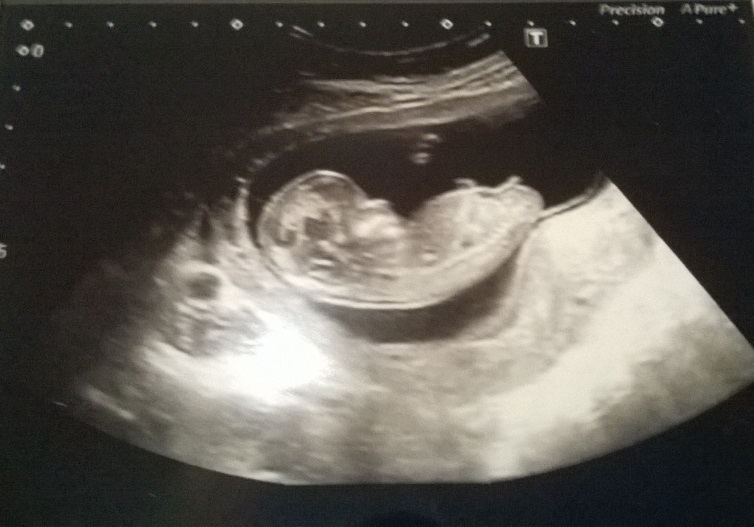

She's a girl! Not what most of you thought, but they thought she was at 16 weeks when my consultant scanned me, and yesterday at 20+4 they said it's as near to definite as it's possible to be, so here she is in her 20+4 glory!

Attachment 24699